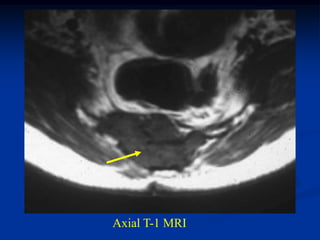

CLASSIC       Case #219

45 year male with chordoma sacrum

Axial T-1 MRI

Axial T-2 MRI